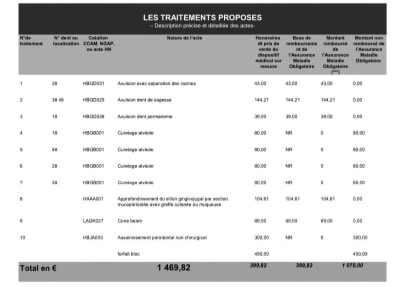

Petit devis reçu récemment, je vous laisse apprécier la variété des actes, histoire de multiplier les fraudes plutôt que de facturer un bloc à 800 balles (je précise qiue ce n'est pas pour de l'AG au passage, juste une avulsion des 4 dds en ambulatoire sans traitement paro) . Ca c'est pas bien, faut pas.

> Petit devis reçu récemment, je vous laisse apprécier la variété des actes,

> histoire de multiplier les fraudes plutôt que de facturer un bloc à 800 balles

> (je précise qiue ce n'est pas pour de l'AG au passage, juste une avulsion des 4

> dds en ambulatoire sans traitement paro) . Ca c'est pas bien, faut pas.

> 1500 balles quatre sagesses même pas incluses mdrrrr